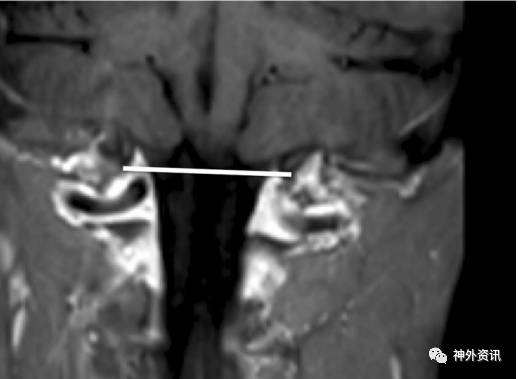

作者回顾性分析50例诊断为Chiari I型畸形的小儿患者,年龄2-21岁,平均9.3岁。在MRI矢状位和冠状位上测量和比较小脑扁桃体下疝情况(图1、2、3、4)。

图4. MRI冠状位成像,无小脑扁桃体下疝。

50例患儿中,48例在MRI冠状位发现小脑扁桃体不对称,左侧扁桃体下疝最大值为20.9毫米,右侧扁桃体下疝最大值为17.4毫米。MRI矢状位上,小脑扁桃体下疝范围从5-27.4毫米不等。5例(10%)患儿在MRI冠状位发现双侧小脑扁桃体下疝至枕骨大孔下长度小于3毫米,19例(38%)在冠状位上一侧小脑扁桃体下疝小于3毫米。但在MRI矢状位上扁桃体下移都超过3毫米,而每例患儿在MRI正中矢状位上的小脑扁桃体下疝均大于3毫米。作者依据测量的结果认为,Chiari I型畸形常常是不对称的小脑扁桃体下疝。如果仅在MRI正中矢状位上测量,小脑扁桃体下疝可能会造成误诊。因此,不应采用单一的MRI矢状位成像诊断Chiari I型畸形小脑扁桃体下疝的程度。